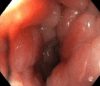

Case summary: Three patients with secondary RLP due to prostatic adenocarcinoma presented with varied clinical features. The first patient, a 76-year-old man with advanced prostate cancer, had rectal pain and incontinence. MRI showed diffuse prostatic invasion and significant rectal wall thickening with a characteristic "target sign" pattern. The second, a 57-year-old asymptomatic man with elevated prostate-specific antigen levels and a history of prostate cancer exhibited rectoprostatic angle involvement and rectal wall thickening on MRI, with positron emission tomography/computed tomography PSMA confirming the prostatic origin of the metastatic spread. The third patient, an 80-year-old post-radical prostatectomy, presented with refractory constipation. MRI revealed a neoplastic mass infiltrating the rectal wall. In all cases, MRI consistently showed stratified thickening, concentric signal changes, restricted diffusion, and contrast enhancement, which were essential for diagnosing secondary RLP. Biopsies confirmed the prostatic origin of the neoplastic involvement in the rectum.